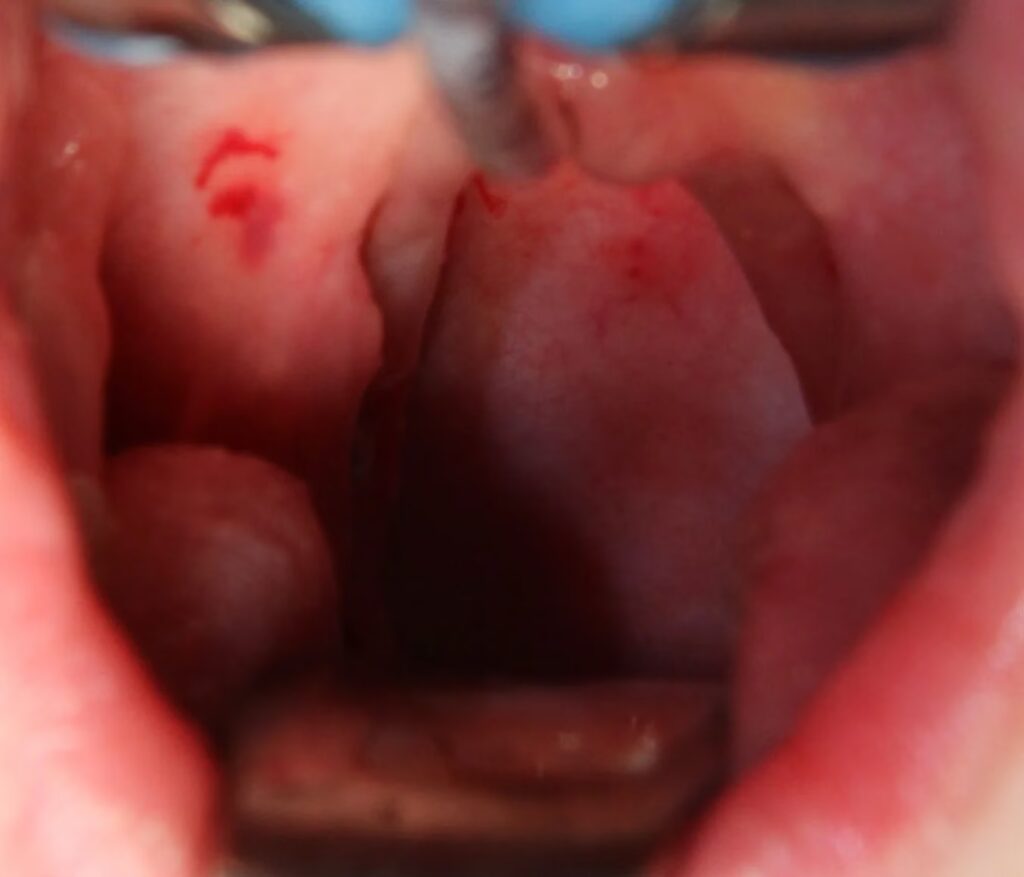

En af de vigtigste ting at være opmærksom på er risikoen for blødning efter operationen. Denne risiko er til stede i op til 7-10 dage efter indgrebet. Derfor er det afgørende at tage den med ro i denne periode. Hvis du ser frisk, rødt blod, skal du straks kontakte din læge eller skadestuen.

Det er meget normalt, at smerten topper omkring 3-5 dage efter operationen. Dette skyldes, at de sårskorper, der dannes i halsen, begynder at falde af, hvilket kan efterlade nerveenderne mere eksponerede og følsomme. Det er en del af helingsprocessen, og smerten vil gradvist aftage derefter.

Ja, dårlig ånde er et meget almindeligt og forventeligt symptom. Det skyldes de hvidlige belægninger (fibrin), der dækker sårene i halsen under helingen. Lugten forsvinder af sig selv, efterhånden som halsen heler fuldstændigt.